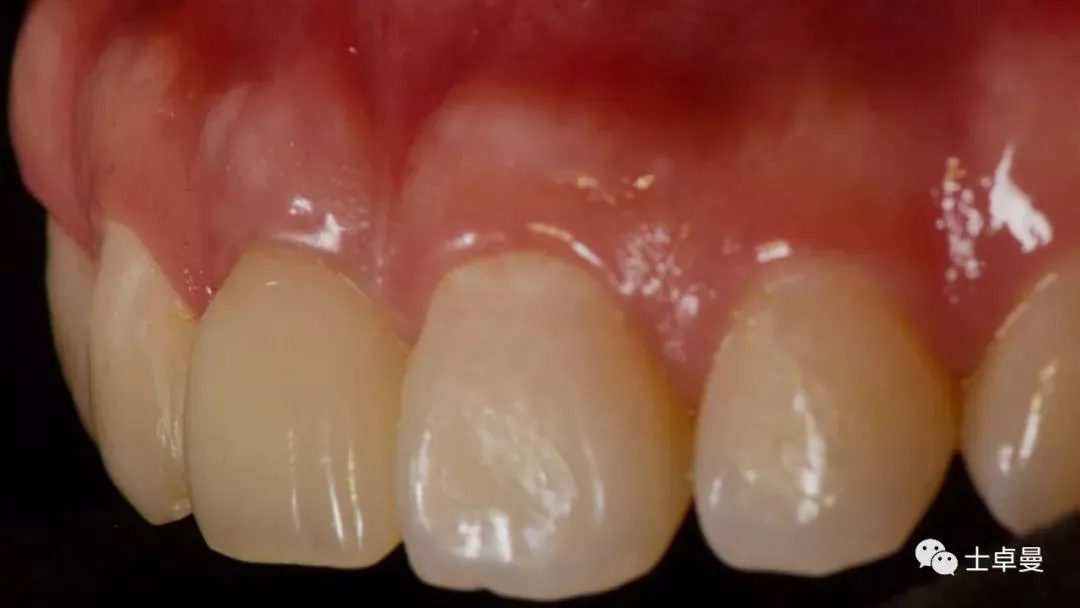

完成永久修复,骨弓轮廓、龈缘及龈乳头形态自然,可见牙龈点彩,修复体外形及色泽可,患者满意。

X线示,永久修复体已就位